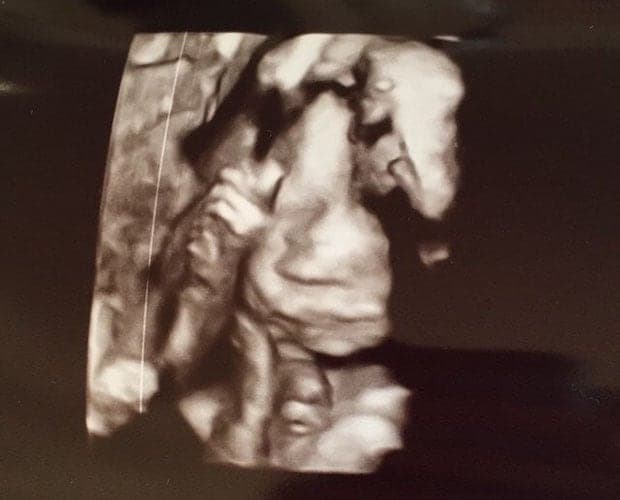

Ultraschallbilder aus dem 3. Trimester (29. bis 40. SSW)

Im dritten Trimester der Schwangerschaft ist das Baby so groß, dass es nicht mehr komplett auf ein Ultraschallbild passt. Nun kann man wunderbare 3D-Ultraschalle des Gesichts machen. In diesem Semester nehmen die Babys nochmal rasant zu und wer Glück hat, kann auf seinem Ultraschall schon erste Gesichtszüge erkennen.